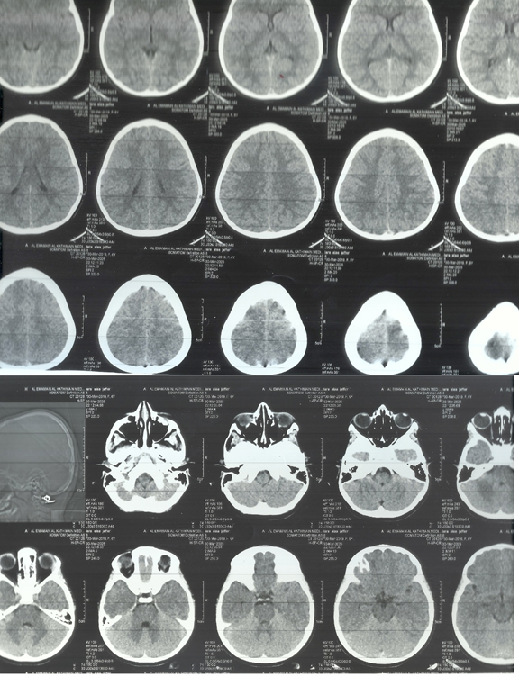

A non-contrast CT brain scan (Figure-2) revealed asymmetric cortical atrophy predominantly in the left posterior frontal and parietal lobes, particularly affecting the perisylvian region. The sulci appeared widened and the underlying white matter volume reduced. There were no calcifications or signs of progressive degenerative disease.

Main brain CT-scan findings Abnormal Findings:

1. Asymmetry of Cortical and White Matter Volumes (Suggestive of Focal Cortical Atrophy)

There is evident left cerebral hemisphere volume loss, especially in the left posterior frontal and parietal lobes, as seen by widened sulci and dilated cortical subarachnoid spaces.

The left lateral ventricle appears slightly enlarged compared to the right (ex-vacuo dilatation), which supports underlying parenchymal volume loss on the left side. This asymmetry is subtle but clear across multiple slices.

2. Subtle Cortical Dysgenesis or Malacia

In the affected left hemisphere, particularly the posterior regions, there appears to be poor differentiation between the gray and white matter, which may reflect focal cortical dysplasia or encephalomalacia. This pattern matches well with focal seizure onset zones in pediatric epileptics.

Figure-2A

Figure-2B

Brain imaging revealed left-sided cortical atrophy, particularly involving the perisylvian and temporoparietal regions.

The left posterior frontal-parietal cortical atrophy, visible on CT, is in a region crucial for language, social cognition, and motor planning. This could explain the patient’s autistic features.

The focal cortical atrophy noted in the left perisylvian and temporoparietal cortex suggests a congenital or early-acquired static lesion, such as focal cortical dysplasia or sequela of perinatal injury. These regions are critical for language and social cognition, and their dysfunction could underlie both autistic and epileptic manifestations.